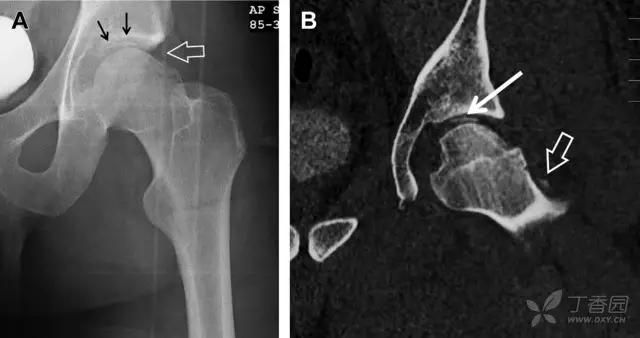

股骨头骨折

股骨头骨折常与髋关节脱位有关。需要注意的是那些既不是因剪力损伤也不是因直接*力暴**作用造成的骨折。这些类型的骨折可能十分轻微。提倡应用 CT 检查,不仅可诊断骨折,而且能评估关节内骨折碎片的位置(图 6)。

图 6 股骨颈骨折伴髋关节脱位。A 股骨头上外侧轮廓缺失(空箭头)注意嵌入上方关节间隙的骨折碎片(黑色箭头)B 冠状位 CT 多维重建(MPR)证实骨软骨碎片(白色箭头)和关节上方的另一个碎片(空箭头)